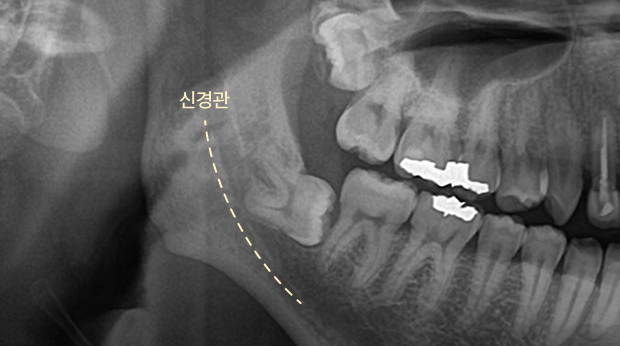

매복 사랑니 발치

고난도 수술 진료

임플란트와 사랑니 발치는 외과적 시술로 잇몸을 절개하는 외과적 시술은

짧으면 짧을 수록 시술 후 붓기와 통증이 최소화됩니다.

치과의사 경력 14년차 구강외과 전문의가 빠르고 안전하게, 아프지 않게 수술해 드립니다.

치과경력 14년차 구강외과 전문의